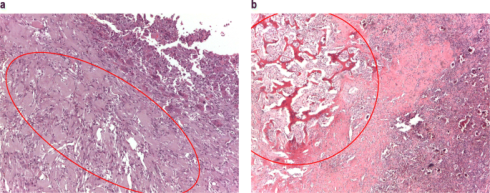

بر اساس اینکه سلولهای سرطانی زیر میکروسکوپ چگونه به نظر میرسند، استئوسارکومها را میتوان به درجه بالا، درجه متوسط یا درجه پایین طبقه بندی کرد. درجه تومور به پزشکان میگوید که چقدر احتمال دارد سرطان به سرعت رشد کرده و به سایر قسمتهای بدن گسترش یابد.

استئوسارکومهای درجه بالا (High-grade osteosarcomas)

اینها سریع ترین انواع استئوسارکوم در حال رشد هستند. وقتی با میکروسکوپ دیده میشوند، شبیه استخوان طبیعی نیستند و بسیاری از سلولهای سرطانی در حال تقسیم شدن به سلولهای جدید هستند. اکثر استئوسارکومهایی که در کودکان و نوجوانان رخ میدهد درجه بالایی دارند. انواع بسیاری از استئوسارکومهای با درجه بالا وجود دارد (اگرچه 3 مورد اول شایع ترین هستند).

این استئوسارکومها دارای کند ترین رشد هستند. تومورها بیشتر شبیه استخوان طبیعی هستند و وقتی با میکروسکوپ دیده میشوند سلولهای تقسیم شونده کمی دارند.

اگر استئوسارکوم تشخیص داده شود، آسیب شناس به آن یک درجه میدهد که بر اساس ظاهر سلولهای تومور، اندازهگیری سرعت احتمالی رشد و گسترش سرطان است. سرطانهایی که تا حدودی شبیه بافت استخوانی طبیعی هستند با درجه پایین توصیف میشوند (و تمایل به رشد آهسته تری دارند)، در حالی که سرطانهایی که بسیار غیر طبیعی به نظر میرسند درجه بالا نامیده میشوند. برای اطلاعات بیشتر در مورد درجه بندی، مبحث مراحل استئوسارکوم را ببینید.